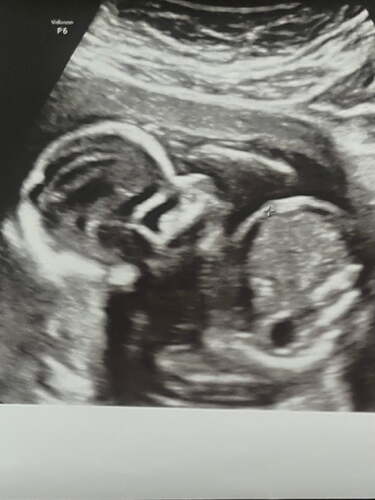

Erkek gibii![]()

Erkek bebiş kesesine benziyo![]()

Bence de erkek![]()